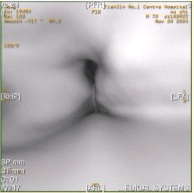

[单选题]患者男,60岁,声音嘶哑半年,CT表现如下图。诊断正确的是A.声门区喉癌B.声门上喉癌C.喉正常表现D.喉结核E.喉乳头状瘤

[多选题]患者男,60岁,声音嘶哑半年,CT表现如下图。有关喉癌,正确的表述是A.喉癌以鳞癌多见B.声门上区淋巴结转移最常见,声门下区次之C.声门区喉癌好发于声